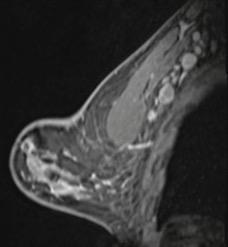

55-year-old woman who underwent screening mammogram and ultrasound 7 days after first COVID-19 vaccination dose. Screening mammogram and US demonstrated unilateral left axillary lymph node with cortical thickness of 5 mm on ultrasound (not shown). BI-RADS category 0 was assigned. Ultrasound from diagnostic work-up performed 7 days later showed no change in lymph node size. BI-RADS 3 was assigned.

Shabnam Mortazavi, M.D., of the University of California at Los Angeles reviewed electronic medical records to identify women with post-COVID-19 vaccination adenopathy found from December 2020 to February 2021. For mammography, Mortazavi considered a node abnormal when its size, shape, or density was deemed disproportionate to other axillary nodes (ipsilateral or contralateral). On ultrasound, she deemed a node abnormal based on subjective assessment for cortical abnormalities, including focal or diffuse thickening greater than 3 mm, as well as nodal prominence compared to the contralateral axilla (when available). For MRI, Mortazavi considered a node abnormal when asymmetric in size and/or number to the contralateral axilla.

Twenty-three women exhibited axillary adenopathy ipsilateral to the vaccinated arm on screening or diagnostic breast imaging, and according to Mortazavi, “13% were symptomatic (axillary lump with possible tenderness).” Meanwhile, the adenopathy was detected incidentally on screening breast imaging in 43% (mammography, 5; ultrasound, 2; both mammography and ultrasound, 1; high-risk screening MRI, 2) and on diagnostic imaging for other reasons in 43% (BI-RADS 3 follow-up for breast finding, 3; screening callback for other reason, 2; non-axillary breast pain or lump, 5). Noting that the median interval between the first vaccine dose and imaging showing the abnormal node was 9.5 days, Mortazavi’s results counted a total of 57% of women with one abnormal node. BI-RADS 2 was assigned in one woman, BI-RADS 3 in 21 (ultrasound in 4–24 weeks), and BI-RADS 4 in one.